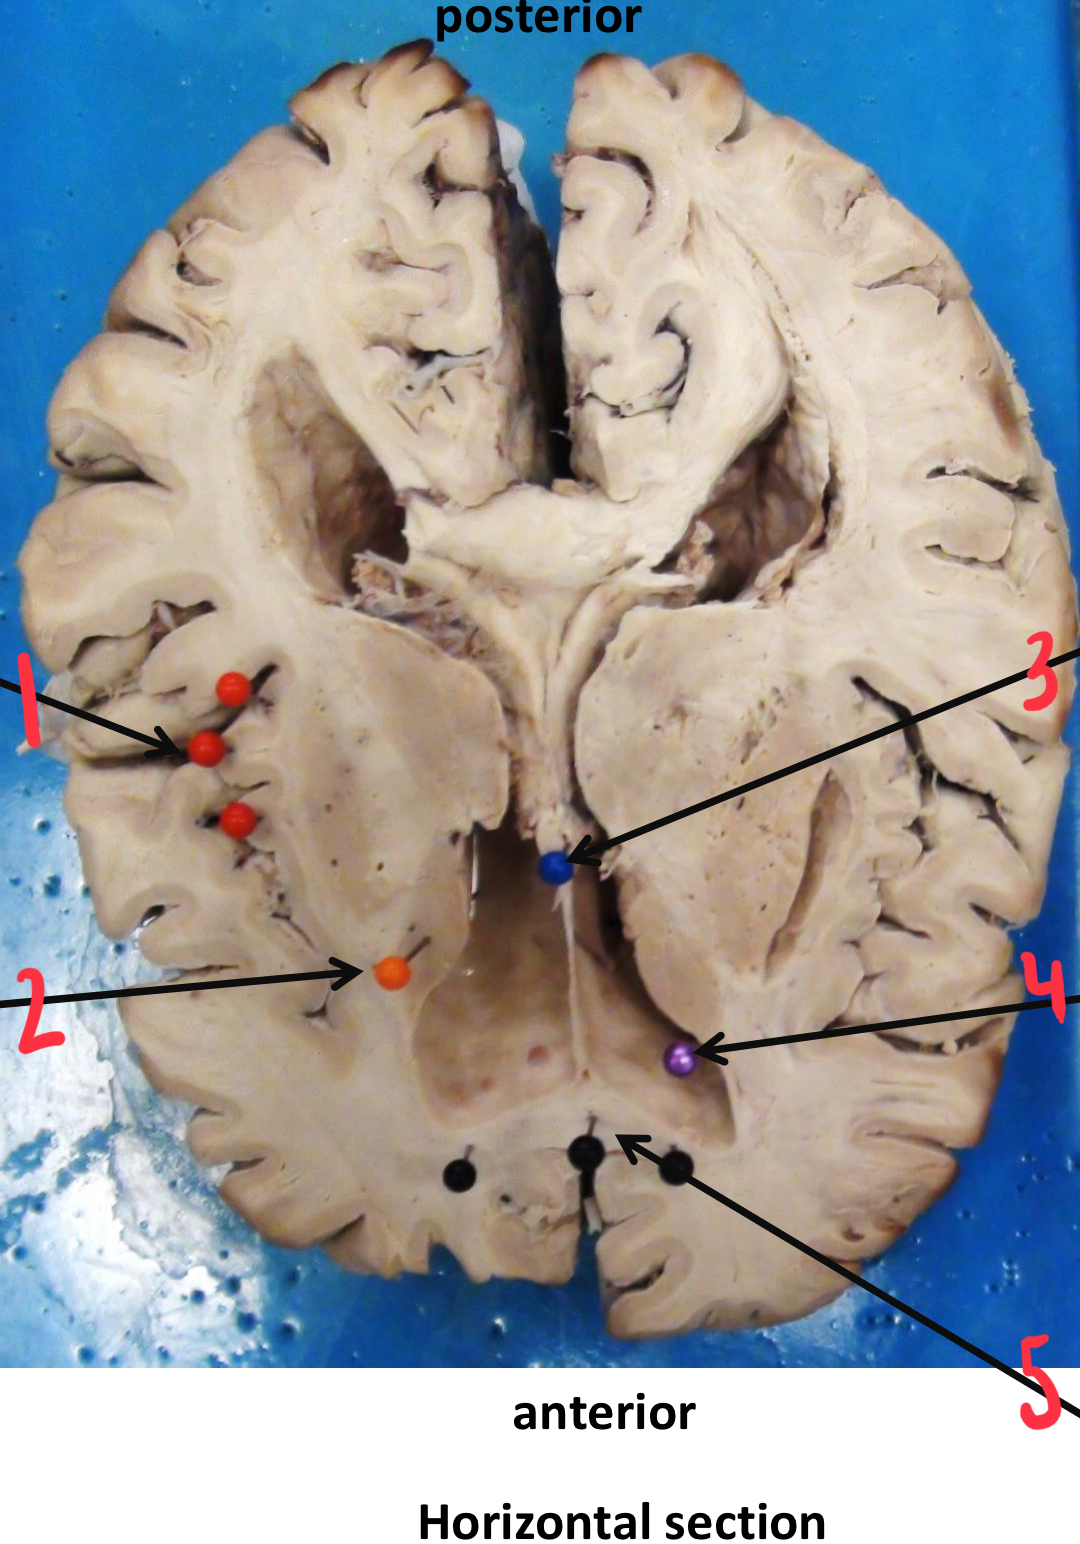

1

insula (island of Reil)

2

caudate nucleus

3

fornix

4

anterior (frontal) horn of the lateral ventricle

5

corpus callosum